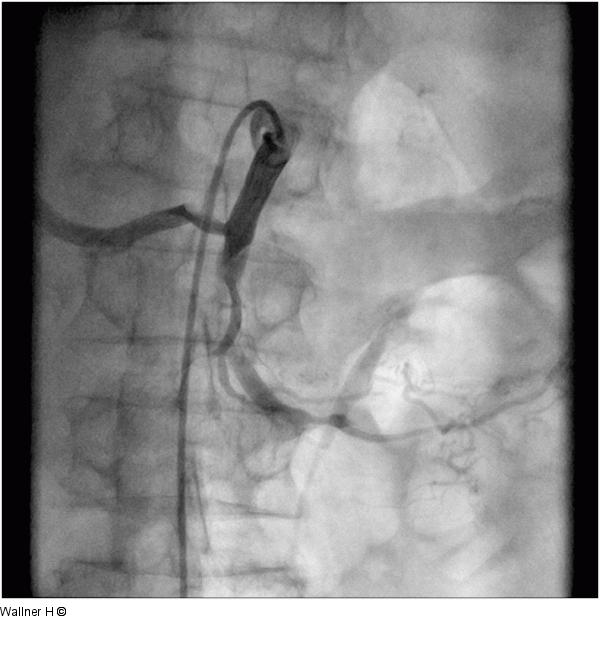

Abbildung 2: A. mesenterica superior Retrograde Darstellung der A. mesenterica superior mit Verschluss ca 5. cm nach dem Ursprung |

Abbildung 2: A. mesenterica superior

Retrograde Darstellung der A. mesenterica superior mit Verschluss ca 5. cm nach dem Ursprung |